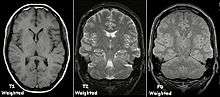

Image contrast may be weighted to demonstrate different anatomical structures or pathologies. Each tissue returns to its equilibrium state after excitation by the independent processes of T1 (spin-lattice) and T2 (spin-spin) relaxation.

To create a T1-weighted image, magnetization is allowed to recover before measuring the MR signal by changing the repetition time (TR). This image weighting is useful for assessing the cerebral cortex, identifying fatty tissue, characterizing focal liver lesions and in general for obtaining morphological information, as well as for post-contrast imaging.

To create a T2-weighted image, magnetization is allowed to decay before measuring the MR signal by changing the echo time (TE). This image weighting is useful for detecting edema and inflammation, revealing white matter lesions and assessing zonal anatomy in the prostate and uterus.